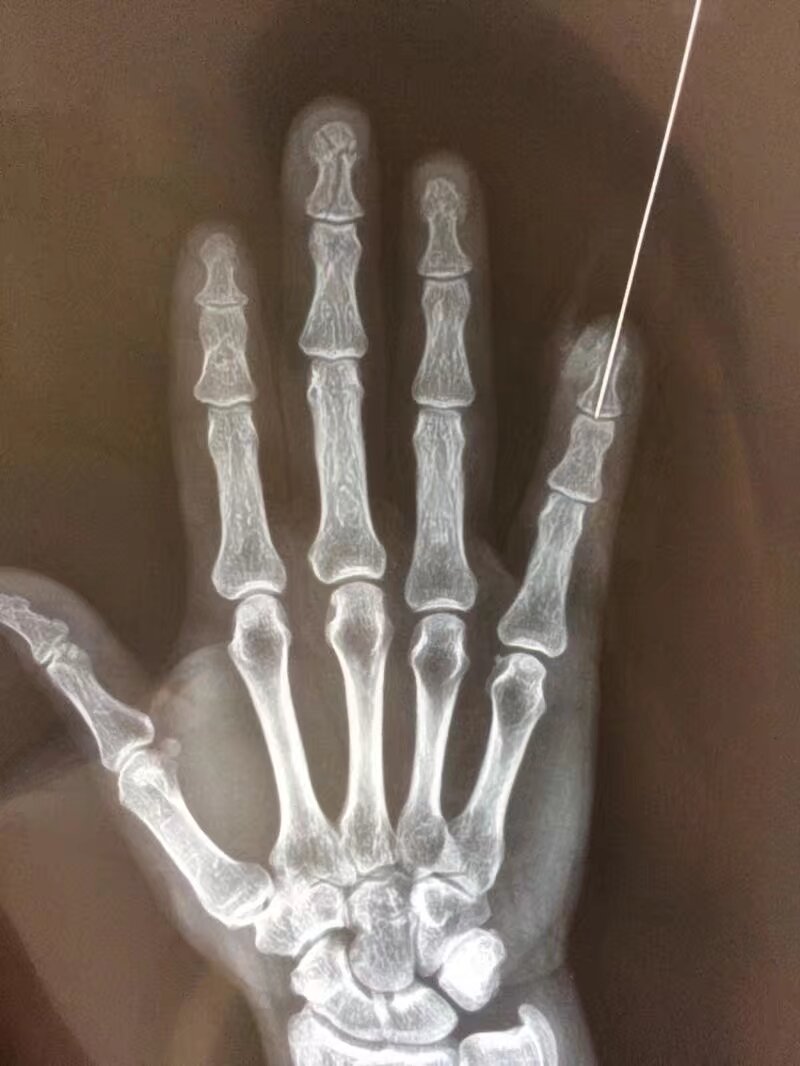

指骨骨折后,克氏针固定是临床常用的治疗方法,尤其适用于手法复位困难或不稳定的骨折,其应用主要体现在以下方面:

2常用固定方式

- 单根克氏针固定:适用于简单横形骨折或斜形骨折,从骨折一端穿入,穿过骨折线至另一端,直接固定断端。

- 交叉克氏针固定:对于斜形、螺旋形或粉碎性骨折,采用两根克氏针交叉穿入骨折端,增加固定稳定性,防止旋转或侧方移位。

- 髓腔内固定:从指骨远端或近端髓腔穿入克氏针,贯穿骨折线,利用髓腔支撑作用固定,适用于长斜形或短缩倾向明显的骨折。

3术后注意事项

- 适时拔除克氏针:一般固定4-6周,根据骨折愈合情况(通过X线检查确认)拆除,避免长期固定导致关节僵硬。